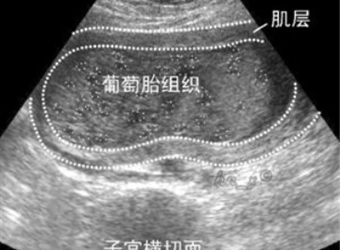

今天闺蜜打电话说怀孕了,但是去医院检查说是葡萄胎,是怪胎吗?好诧异呀,从来没有听过“葡萄胎”难道真的是什么怪胎.